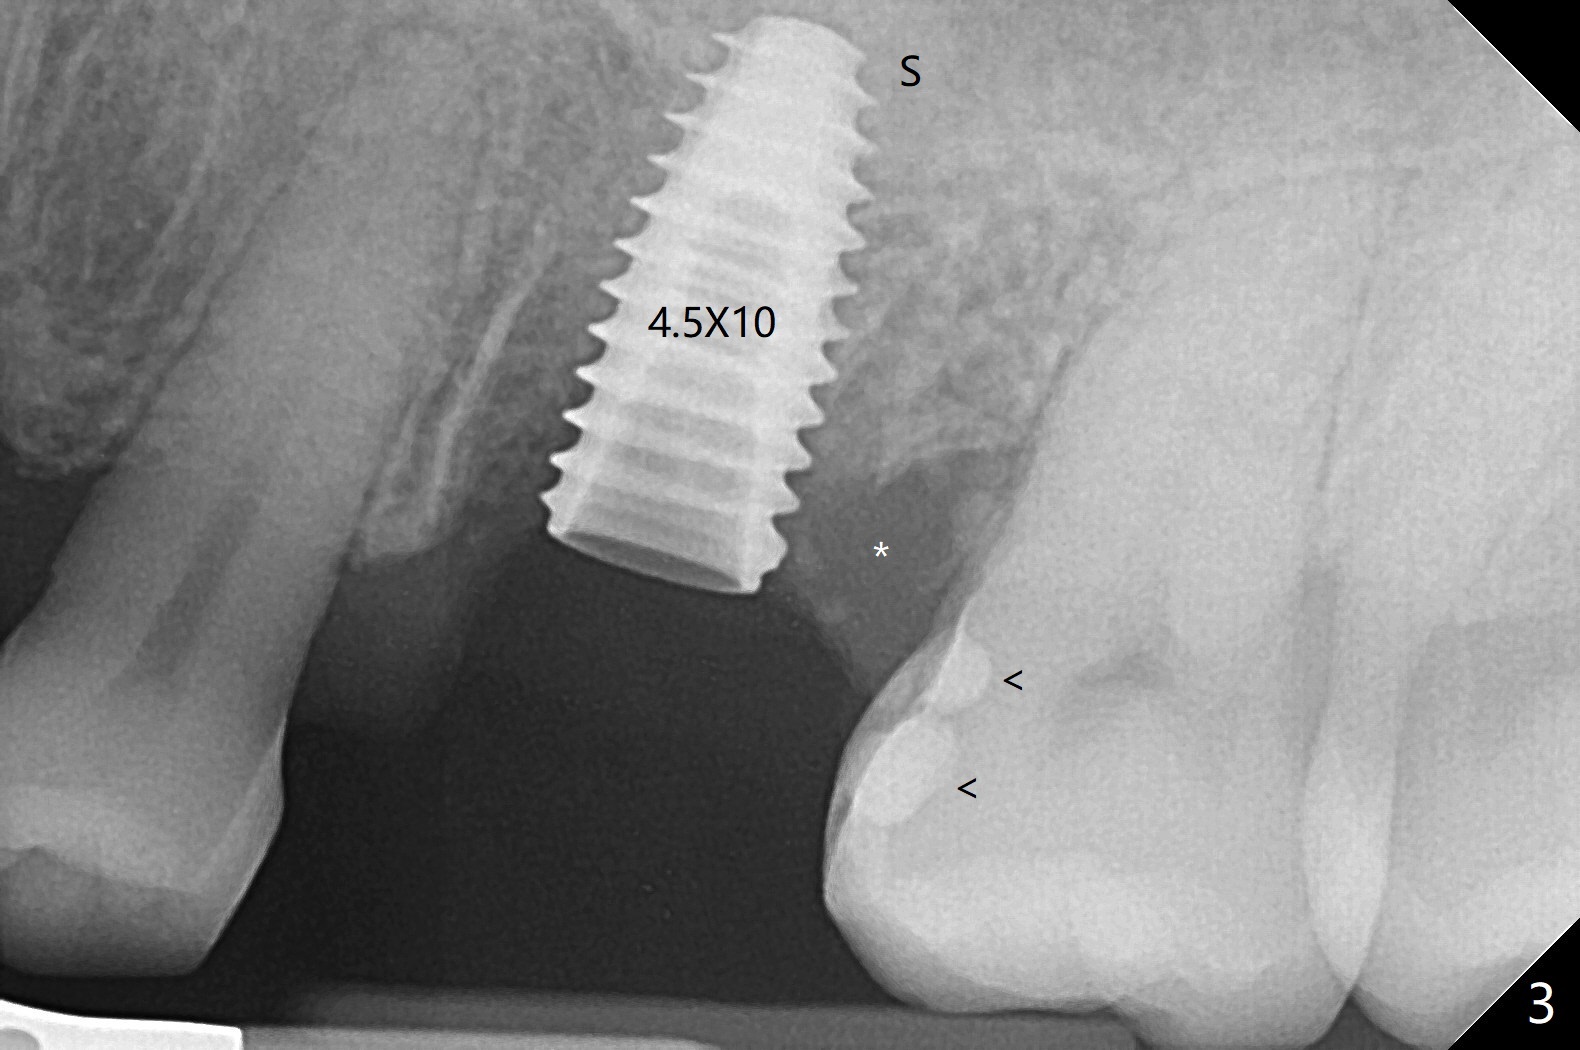

虽然没有保留左上6牙根,但是导板好像帮助钻洞(O)正好位于中隔当中(图一,二)。使用4.5(不是4.0)x10毫米钻头后,粘性骨粉和报废植体完成上颌窦提升术(图三:S)。拔除第一磨牙后发现第二磨牙近中面龋齿,立刻进行保守修补(图三:箭头);两个磨牙之间还有骨质吸收(*)。放置正式植体(10Ncm)后(图四),三个牙槽窝填入骨粉,包括近中颊侧(MB)和远中颊侧(DB),这时磨牙间缺损初步填补(*),然后放置基台以及基台周围骨粉,进一步充填磨牙间缺失(图五:*)。术后临时牙冠脱落两次,病人自己放回去,术后一周取出牙冠,骨粉还在(图六),腭侧有单纯疱疹病变(图七:>),开抗病毒漱口水处方,然后使用临时粘固粉。术后7个月15号牙近中牙槽嵴增高大约1.4毫米(图八:空箭头,从近中最颈部树脂算起)。术后七个月临时牙冠一直使用,防止食物坎塞,有利于骨质再生。术后7个月基台在口内没有更动(术中手拧紧),牙冠口内粘固,少量粘固剂遗留(图八:^)。牙冠/基台取出,去除粘固剂,牙冠/基台就位,用扳手拧紧(30 Ncm),基台与植体仍保持完全接触(图九)。只要植体植入角度好,没有倒凹,牙冠/基台再次就位就没有问题。